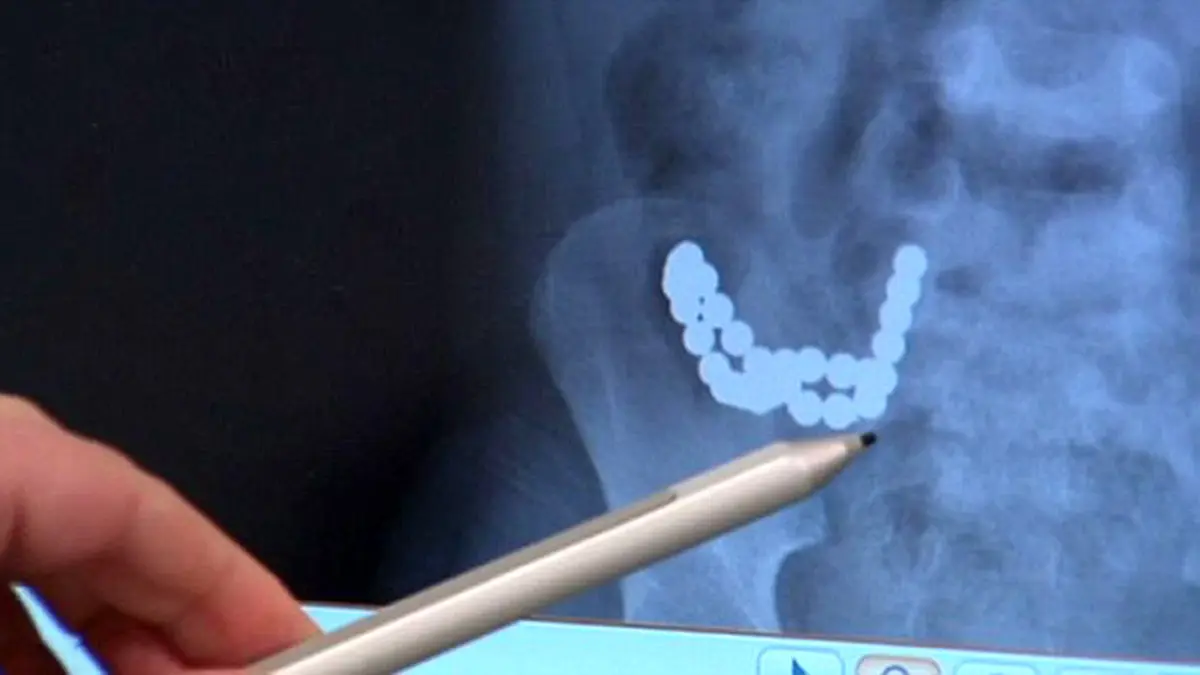

این پسر 30 آهنربا قورت داد!+ عکس رادیولوژی

به گزارش گروه ترجمه رکنا، عکس رادیولوژی باور نکردنی از شکم این پسر 5 ساله، مگنت‌ها را نشان می‌دهد که داخل شکم او در یک ردیف به هم چسبیده‌اند. کودک با قورت دادن این آهنرباها آنها را آبنبات پنداشته بود جان خود را به خطر انداخته و از درد به خود می‌پیچید.

کودک که نوا نام دارد به سرعت به بیمارستان کودکان در ملبورن رسانده شد و 6 ساعت طول کشید تا جراحان آهنرباها را از بدنش خارج کنند. آهنرباها برای چسبیدن به هم در روده نوا حرکت کرده و باعث ایجاد 12 سوراخ در روده‌ او شده بودند. جراحان مجبور شدند قطعه‌ای از روده نوا را که آسیب شدیدی دیده بود خارج کنند. به گفته آنها، کمی تاخیر در رسیدن نوا به بیمارستان می‌توانست پایان کار او باشد.